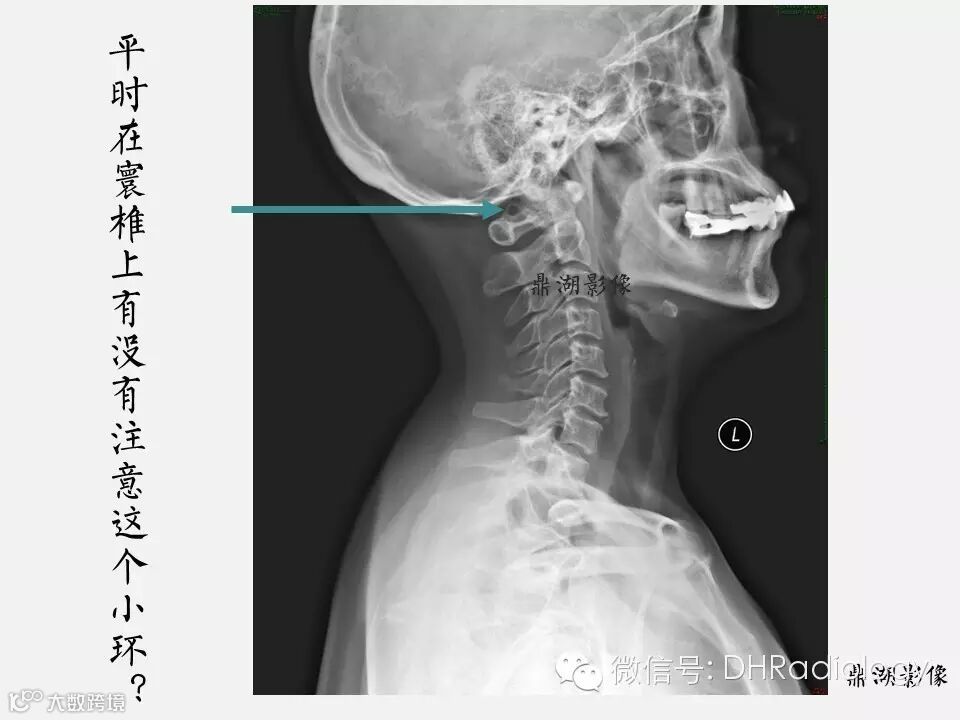

【聚沙成塔】教你一个有意思的变异——寰椎沟环畸形

这是什么呢?

有什么临床意义?

不要觉得这病少见,不瞒各位,小编也是这种畸形/(ㄒoㄒ)/~~。